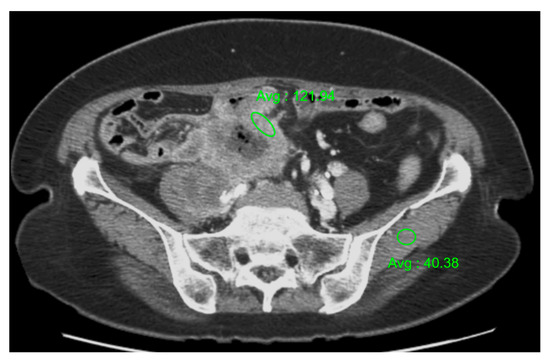

2.4. Image Analysis

| Age (y)/ Sex | Clinical Presentation | Radiologic Studies | Tumor Location | Morphologic Type | Maximum Wall Thickness (mm) | Enhancement Pattern of the Tumor * | Enhancement Degree † | Tumor Necrosis | LAP (Number/Diameter (mm)) ‡ | LAP Necrosis | Adjacent Organ Invasion | Distant Metastases |

|---|---|---|---|---|---|---|---|---|---|---|---|---|

| 70/F | Abdominal pain | CT, US | Sigmoid colon | Bulky mass | 44 | Heterogeneous | Well (3.01) | Yes | 0/NA | NA | Right ureter and ovary, ileum, urinary bladder, iliopsoas muscle, and uterus | No |

| 59/M | Hematochezia | CT, PET-CT | Rb | Circumferential wall thickening | 24 | Homogeneous | Moderate (1.22) | No | 10/21 | Yes | Levator ani muscle, prostate, urinary bladder | No |

| 67/F | Hematochezia | CT | Ra | Eccentric wall thickening | 14 | Homogeneous | Moderate (1.36) | Yes | 2/12 | Yes | No | No |

| 92/M | Hematochezia, constipation | CT | Rb | Bulky mass | 44 | Heterogeneous | Well (1.53) | Yes | 2/17 | Yes | Prostate | No |

| 54/F | Fever | CT, US, PET-CT | Ra | Bulky mass | 49 | Heterogeneous | Well (2.02) | Yes | 8/21 | Yes | Uterus | Liver |

| 86/M | Hematochezia | CT | Rb | Circumferential wall thickening | 25 | Homogeneous | Well (2.36) | No | 1/25 | Yes | Levator ani muscle | No |

| 76/M | Abdominal pain | CT | Ra | Circumferential wall thickening | 14 | Homogeneous | Moderate (1.23) | No | 1/8 | No | No | No |

| 54/F | Hematochezia | CT | Rb | Circumferential wall thickening | 19 | Homogeneous | Moderate (1.16) | Yes | 1/12 | Yes | No | No |